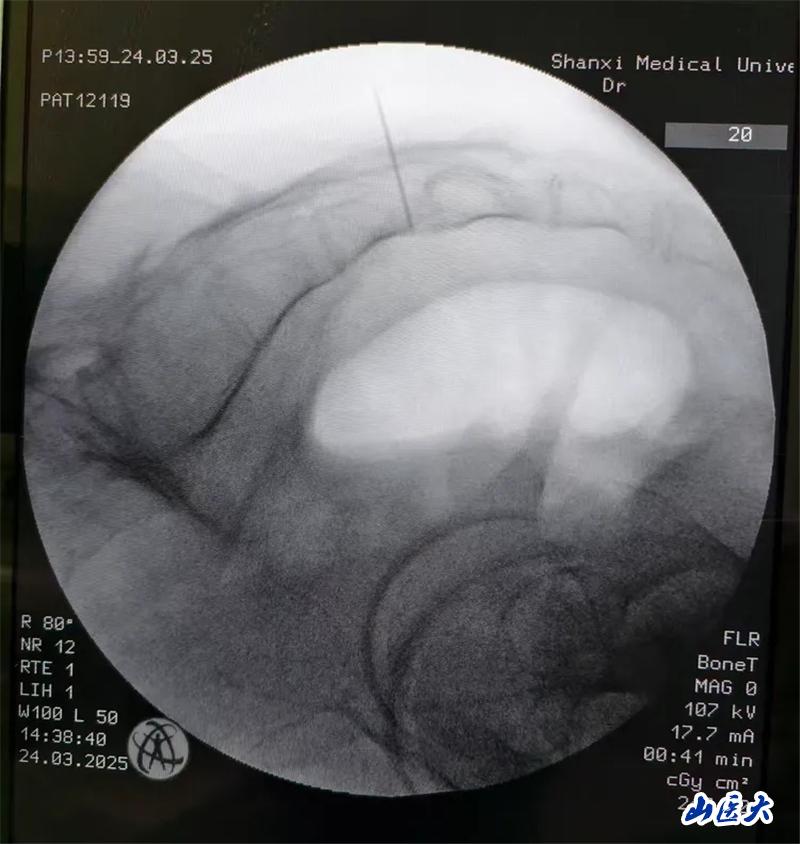

患者是一名中年男性,有著4年以上的尿頻、尿急和排尿困難癥狀,長期和尿不濕、尿管為伴,苦不堪言!做尿動力檢查,診斷為:神經(jīng)源性膀胱和膀胱過度活動癥。王璟琦主任醫(yī)師充分評估病情后,為其進行了骶神經(jīng)調(diào)控術(shù)治療,術(shù)后下尿路癥狀明顯改善。手術(shù)過程中,患者取俯臥位,顯露肛門,便于術(shù)中觀察電刺激效果。首先,經(jīng)尾骨尖測量定位確定s3的位置:沿骶骨中線,自尾骨尖向上測量9cm,旁開2cm,為S3骶孔對應體表處。之后在C型臂的引導下準確穿刺S3孔,通過導絲將刺激器導線穿入S3孔內(nèi),并根據(jù)術(shù)中對骶神經(jīng)刺激后的效果,將導線放入最佳深度。最后,將導線從皮下穿出連接電刺激器。電刺激信號測試滿意,三周體外實驗,患者排尿改善將二期植入。